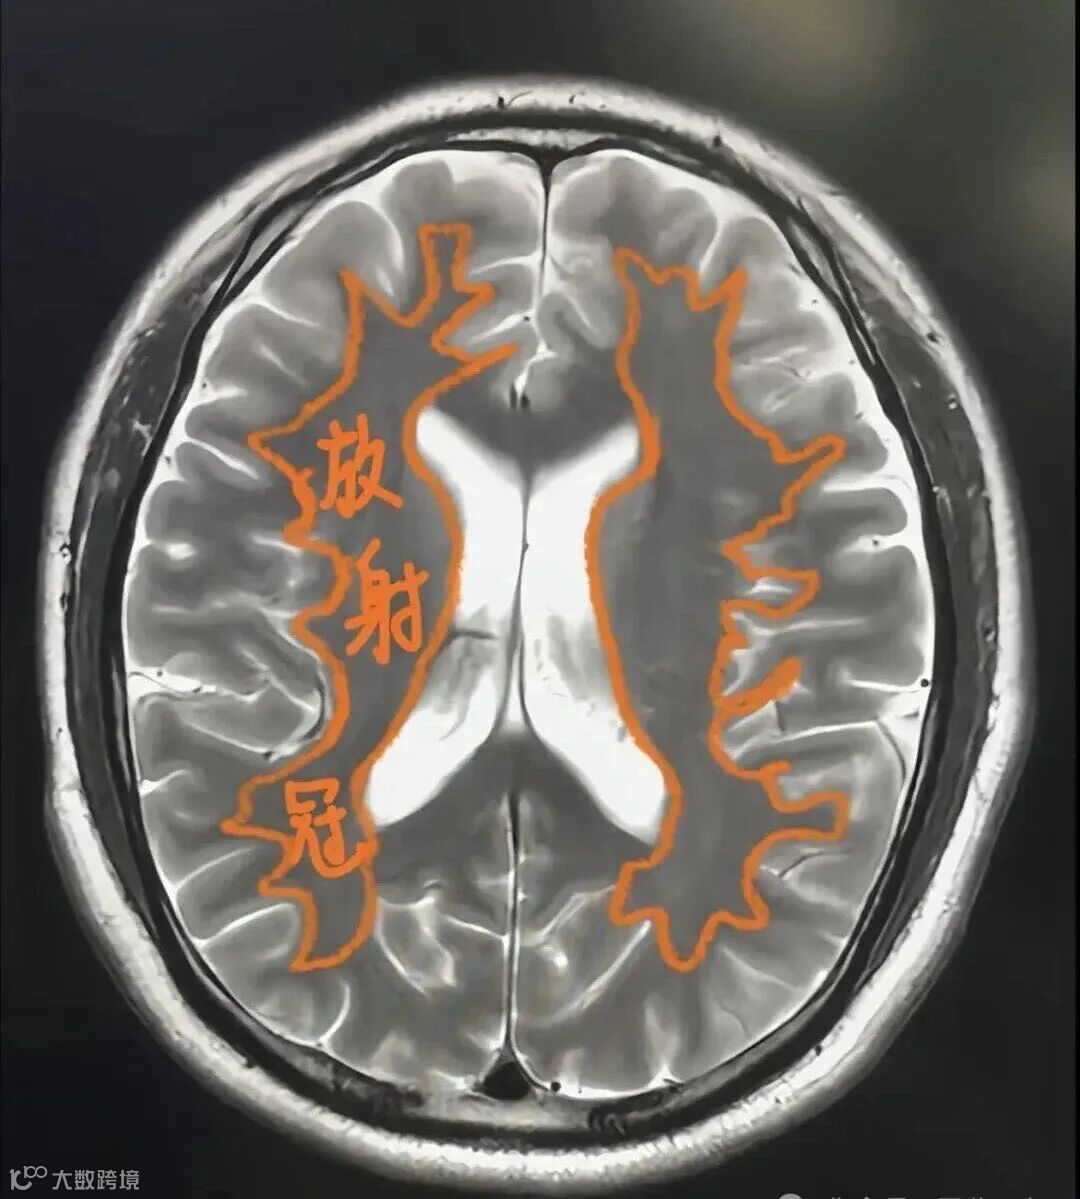

放射冠:指两侧侧脑室周围的脑白质层面。